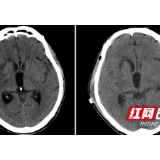

患者颅骨修补前、修补后的头部影像。

3月2日,54岁的湖南宁乡男子周某突发意识障碍伴左侧肢体活动障碍,在当地医院做头部CT检查提示:右侧基底节出血、压迫脑室、中线偏移明显,随即转入湖南省人民医院神经外一科病房。